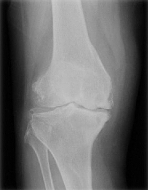

人工膝関節置換術は年間約8万件行われている手術で、手術の対象となるのは、関節の間にある軟骨や半月板がすり減ったり、変形することで痛みや機能障害を招く変形性膝関節症と診断された方々です。もともと骨の形がO脚の人や、若い時のケガが原因になることもありますが、一番は老化、使いすぎです。高齢者に多いのはこのためで、筋力が落ちてきたり、体重が増えることで症状が深刻になってきます。

人工膝関節置換術の内容は、傷ついてしまった膝の軟骨や骨を表面的に切り取り、膝の変形を矯正し、金属やセラミック、ポリエチレンなどでできた人工関節に置き換える手術です。手術は1時間程度で終わります。膝がとても痛くて、変形性膝関節症の方やリウマチの方が手術の適応になります。